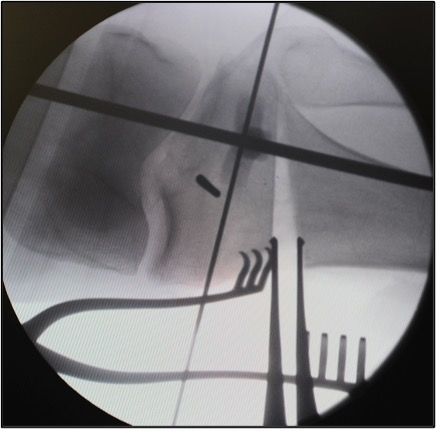

Distraction of the osteotomy (multi-chisel technique) and plastic deformation of the lateral hinge with the distractor

Introduction of a first chisel (20 mm size) below the K-wires. This is advanced under image intensifier control up to around 5 mm before the lateral cortex. The next chisel (20 mm size) is advanced below it, also up to around 5 mm from the cortex. Thereafter, a further chisel (25 mm size) is carefully advanced between these two chisels up to around 15 mm from the lateral cortex. The chisels should be introduced slowly (Fig. 7a).

This creates a plastic deformation of the hinge with controlled microfractures that taper parallel to the first two chisels. With larger corrections another 2−4 chisels can be introduced; each one is introduced a little less far than the previous ones. Thereafter we remove the two K-wires and the chisels. At this time in the operation the lateral hinge should still be sufficiently stable under image intensifier control and should not be shifted. However, if the osteotomy tools are advanced too far it can result in uncontrolled fractures of the hinge and even opening up or shifting of the osteotomy at the lateral hinge.

As the next step, an arthrodesis distractor is fully inserted dorsally and slowly distracted. We close and open the distractor carefully several times. This gives an indication of the elasticity of the osteotomy. If there is still a lot of resistance it can be either due to an insufficient release of the superficial medial collateral ligament or to an incomplete dorsolateral osteotomy. With an incomplete osteotomy the dorsolateral cortex can be further weakened with a rounded chisel under image intensifier control. The hinge should have good mobility but must be preserved.

Control of the correction in the frontal and sagittal plane

Now we position the knee in extension, support the heel with a roll. The knee should be fully extended. This is particularly important in knees with a preoperative extension deficit. Any extension deficit hast to be corrected during the operation. This is achieved by a reduction of the tibial slope by pushing the knee down in full extension by the assistant. We control the change of the tibial slope with the two anterior K-wires (Fig. 7b).

Due to the triangular form of the tibia the biplanar osteotomy is always opened about 30% more dorsally than anteriorly [25]. Now we measure the size of the correction on the central tibia edge and compare it against our plan (Fig. 7c).

Then the intraoperative Mikulicz line in full extension of the knee is documented under image intensifier control. The anterior K wires introduced at the start of the operation accurately show us any changes to the rotation and the slope (Fig. 7d). The use of computer-assisted navigation is helpful in complex two-dimensional corrections (Fig. 7e).